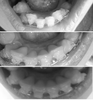

Давно здесь не писала... Боли ушли примерно через месяц после установки, ночью я порой просыпалась от дикой боли - челюсти резко смыкались, будто судорогой, но это продолжалось не долго, а месяца через полтора я вообще забыла про свои брекеты))) Периодически после визитов к своему ортодонту зубки могли поболеть пару дней, но это было или из-за смены резинок, или из-за новых цепочек, и это меня не беспокоило). Жвачку не жую, откусываю разве что хлеб, твердые продукты, фрукты - всё режу на кусочки и кушаю спокойно) Отваливался один брекет - внезапно это случилось, при чем тот, в котором закреплена дуга, я перепугалась, но всё оказалось не так страшно - брекет на место приклеили, никто не пострадал))) Я переживала, помню, что не могла спокойно смыкать губы, закрывать рот, - сейчас всё удается!)) Из наблюдений близких - говорят изменилась форма лица, да я и сама наблюдаю это) Но изменения происходят только в лучшую сторону)) Вообще хочу сказать, если сейчас эту запись читает человек, который подумывает ставить брекеты или не может решиться - РЕШАЙТЕСЬ!!! Это того стоит! Я прошла через удаление 4х зубов, брекеты мне надели сразу на обе челюсти, но результат, не заставит себя ждать, и он обязательно будет хорош, что не может не радовать!!))

Olmi , пока нет, мой орт говорит, что закрывать промежутки будем позже) Но они уже сейчас меньше, чем были... Мне удаляли 4ки на верхней и 5ки на ниж, и мне кажется, что на обеих челюстях промежутки уменьшаются в равной степени...)